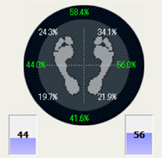

バランス表示

前後・左右のバランスを数値化して表示します。